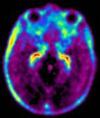

FDG

近年来,利用正电子发射断层扫描(PET)技术诊断肿瘤及癌症得到广泛的关注和应用。含氟化合物以及19F NMRPET诊断技术发展的核心,这是因为正电子发射同位素18F的半衰期相对较长(t1/2=110min)。[18F]-2--脱氧葡萄糖(FDG)是应用最为广泛的癌症诊断PET探针。研究表明,使用FDG进行PET显影在检测多种类型的肿瘤细胞方面比CTMRI显影技术更有效。